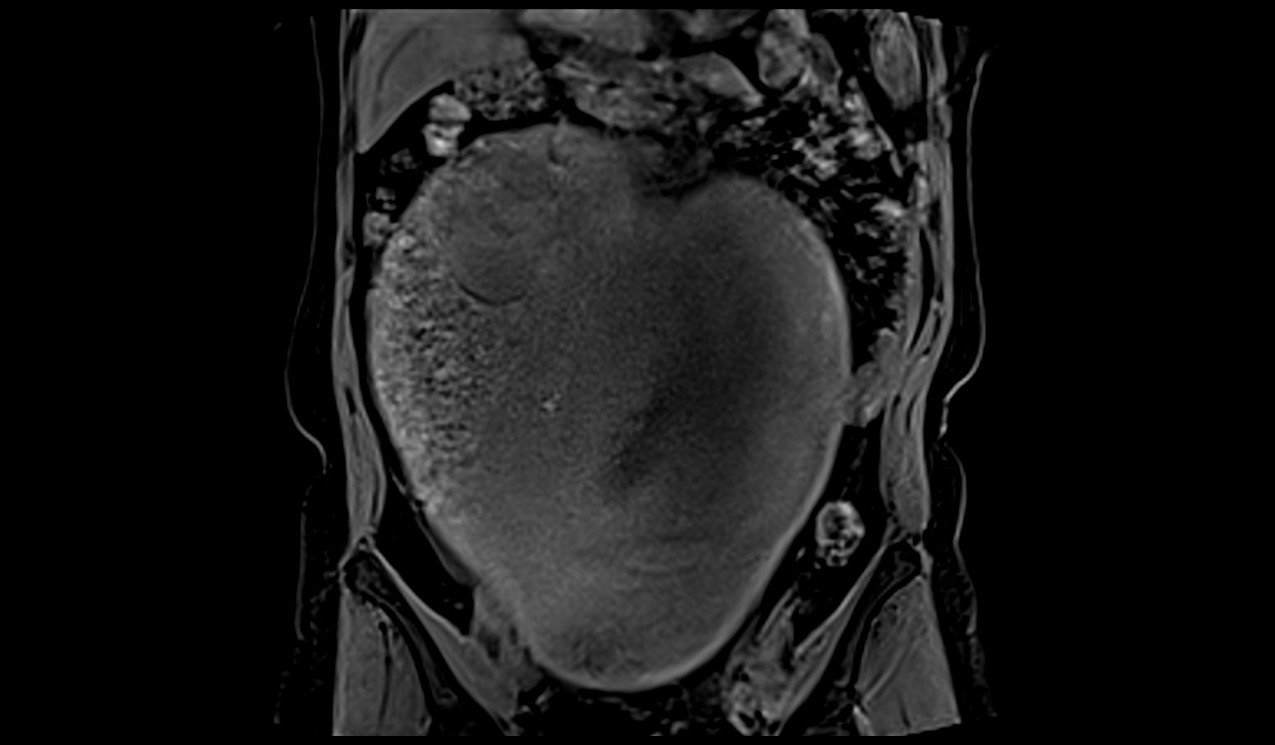

MRI Large abdomen and Pelvic Masses axial t1 dynaic image 1 - MRI